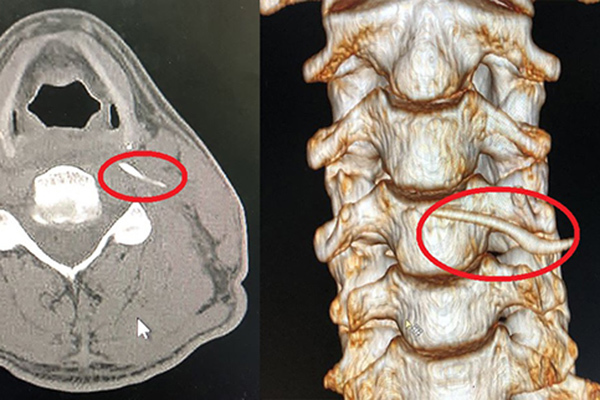

Bé 3 tuổi suýt chết vì chẩn đoán nhầm viêm họng

Mảnh xương chỉ dài 2cm nhưng gây tụ dịch mủ trong họng, đâm vào ống động mạch đốt sống cổ của bệnh nhi. Nhiều lần đi khám trước đó, bé được chẩn đoán viêm họng.